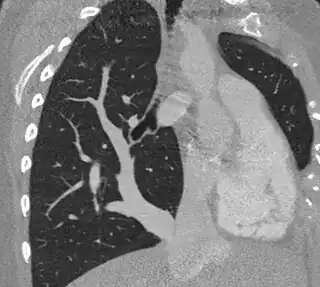

Síndrome de la cimitarra

El síndrome de la cimitarra, también conocido como síndrome de drenaje venoso anómalo del pulmón derecho, es una enfermedad congénita inusual que consiste en un mal drenaje de las venas pulmonares derechas a la vena cava inferior, aurícula derecha, que con frecuencia se asocia a hipoplasia del pulmón derecho y de la arteria pulmonar derecha. También se han descrito malformaciones bronquiales, dextrocardia e irrigación arterial anómala de la aorta hacia el pulmón derecho.

Así mismo, su imagen radiológica es clave, ya que recuerda a la de un sable turco en la radiografía de tórax simple. Suele estar acompañado por hipoplasia pulmonar derecha y dextrocardia. Su imagen radiológica corresponde a la visualización de un gran vaso venoso (drenaje de las venas pulmonares) anómalo que recorre la silueta cardíaca derecha para drenar en la vena cava inferior por arriba o por debajo del diafragma.